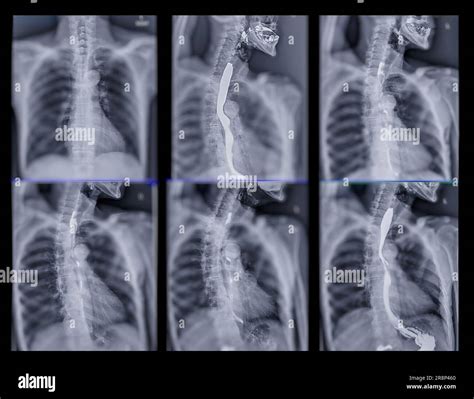

A Video Swallow Study, also known as a modified barium swallow study, is a diagnostic procedure that uses fluoroscopy to observe the swallowing process in real-time. During the study, the patient ingests barium-coated food or liquid, which makes the swallowing structures visible on X-ray images. This allows healthcare professionals to identify any abnormalities or obstructions in the swallowing pathway.

2. Barium Administration: The patient is given barium-coated food or liquid to swallow. The barium makes the swallowing structures visible on the X-ray.

3. Swallowing Observation: The healthcare provider observes the swallowing process on a monitor, noting any abnormalities or obstructions.

Interpreting the results of a Video Swallow Study involves analyzing the fluoroscopy images to identify any abnormalities in the swallowing process. Key areas of focus include:

• Pharyngeal Phase: The movement of the bolus (food or liquid) through the pharynx and the coordination of the pharyngeal muscles.

• Esophageal Phase: The movement of the bolus through the esophagus and into the stomach.